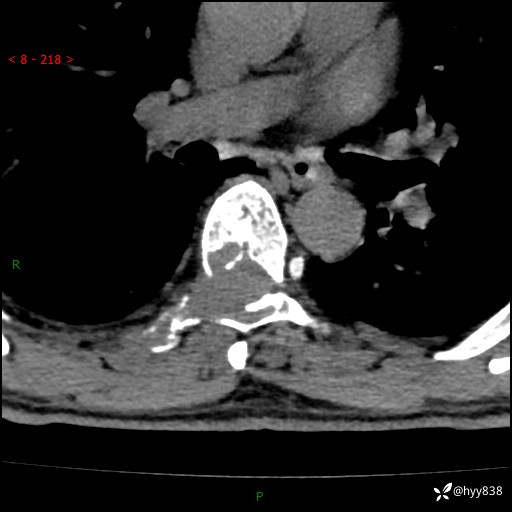

辅助检查:CT MRI

胸椎CT平扫(骨窗+软组织窗)